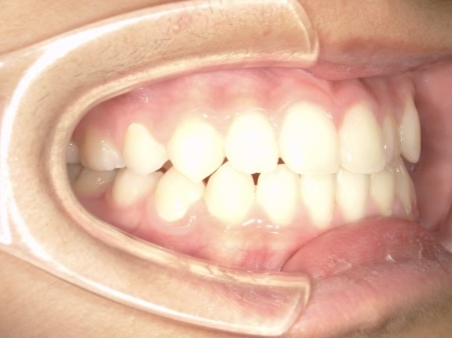

治療中④ 小4:10y1m

左上3が八重歯で萌出中